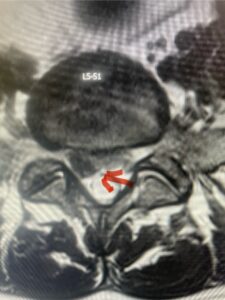

In this next case, this patient is a 47 year-old female who presents with intractable low back pain with severe pain, numbness, and weakness in the right lower extremity that had gotten progressively worse over a year. The patient had failed conservative management including physical therapy and epidurals. She was noted to have ⅘ weakness of plantar flexion. MRI demonstrated a large right L5-S1 disc herniation with severe compression of the descending right S1 nerve root (Fig 3). It was decided to perform a right L5-S1 hemilaminectomy for removal of the disc fragment and decompress the S1 nerve root. When you expose the disc, one must be certain to release any anterior adhesions to the nerve root in order to prevent a dural tear during retraction of the nerve root. It is also important to make sure during exposure and you finally encounter the dura after removing the ligamentum and fat, to make sure you are looking at the nerve root and not the main trunk of the thecal sac because if you don’t you can avulse or damage the nerve root if you retract the wrong structure.

Fig. 3a: Sagittal and axial T2-weighted lumbar MRI images demonstrating large right L5-S1 disc herniation (red arrows)

Fig. 3b

We found a massive subligamentous herniation which had to be revealed by having your partner retract the freed nerve root with a nerve root retractor and putting slight downward pressure on the more medial and anterior disc space. There is nothing more satisfying when the jelly (disc fragment) of the annulus (donut) comes squirting out and you remove a large chunk of disc material that clearly was stretching the ligament membrane and compressing the nerve root. This does cause back pain in addition to radiculopathy not only by the component of mechanical compression but also the stretching of the nerves within the ligament. We performed this surgery and noted that the nerve root was a very angry red color or hyperemic and we removed a large subligamentous fragment. The patient had improvement of her preoperative radicular symptoms.